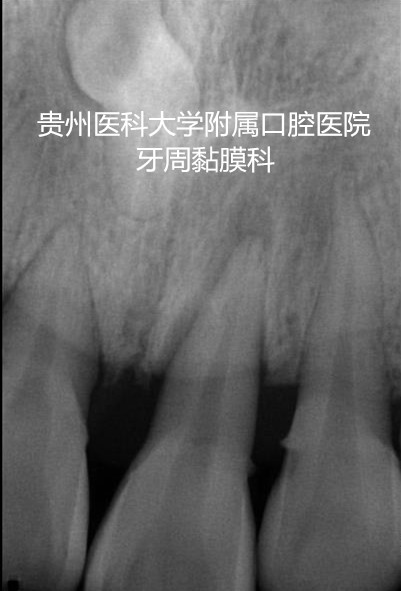

陈老师是一名重度牙周炎的患者,上下前牙多颗牙松动严重,经过牙周系统治疗后,牙周的炎症得到控制,但上下前牙的松动仍影响咬合,经过williamhill官网附属口腔医院牙周黏膜科的高强度纤维带松牙固定后,将多个松动牙连成一个新的咀嚼单位,有利于牙周组织的愈合,陈老师非常满意。

一次轻微车祸致使26岁唐某门牙松动,怎么办呢?对美观要求比较高的她因接受不了钢丝结扎,来到了williamhill官网附属口腔医院牙周黏膜科求诊。经医生检查,唐某的21号牙属于牙脱位,需要做松牙固定术,必要时需要根管治疗术,故其决定做牙周黏膜科正在开展的临床新项目——高强度纤维带松牙固定术,既保证松动牙的有效固定,又在一定程度上保证美观。唐某术后效果良好,等待8周左右唐某就可以拆除固定材料啦!

同样的外伤让刘某前门牙一颗缺失,两颗松动。对美观要求高的他一天也忍受不了缺失门牙的痛苦。在等待种植的过程中,刘某来到williamhill官网附属口腔医院牙周黏膜科,利用自己的离体牙进行高强度纤维带松牙固定术,这不仅恢复了美观和部分功能,还使其他外伤导致的牙齿松动得到了宝贵的愈合时间。在等待拔牙创愈合的时间内,刘某的美观基本不受影响,他对效果非常满意。拔牙即可至种植II期修复前,高强度纤维带松牙固定术可以保证患者的美观和功能,成功渡过这个过渡期。